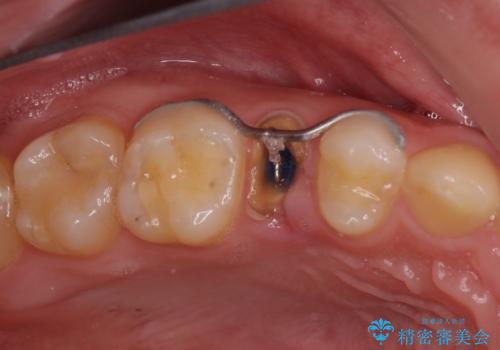

- 左下4番目の歯がしみるので診てほしいと来院され、検査したところ虫歯と診断した症例です。

冷たいものはしみますが、持続痛、自発痛、咬合痛等はありませんでした。

虫歯の部位が歯の隣接部であったため、虫歯除去後、セラミックインレーによる修復処置を行いました。